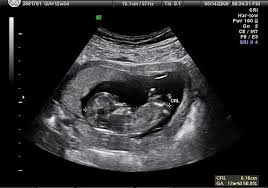

Sedangkan di usia 20 minggu kehamilan, hasil usg sudah mulai menunjukkan adanya hidung, kaki, tulang belakang, jantung janin, mata, dan jenis kelamin. Oleh karenanya, tingkat kesalahan identifikasi janin perempuan lebih besar daripada janin laki2. Cara membaca hasil usg jenis kelamin bayi perempuan anda kemungkinan mengandung bayi perempuan apabila hasil usg menunjukkan: Melalui usg, dokter dan ibu hamil dapat mengetahui kondisi janin dalam kandungan. Namun tak selamanya pemeriksaan usg ini bisa menebak jenis kelamin bayi dengan akurat. Hal yang membedakan keduanya dalah kejelasan gambar janin yang nampak pada alat usg. Saking bingungnya sampai tanya pendapat. Manfaat usg 3 dimensi sama seperti usg 2 dimensi, usg 3 dimensi menggunakan gelombang suara berfrekuensi tinggi dan peranti lunak (software) khusus untuk menangkap gambar.

Tidak hanya untuk melihat jenis kelamin bayi, tetapi juga bisa melihat pertumbuhan dan perkembangan bayi dalam kandungan. Selama kehamilan, usg jadi alat paling penting untuk memeriksa pertumbuhan, perkembangan, posisi, dan gerakan bayi.usg juga memberi kesempatan orang tua untuk melihat bayi mereka. Bedanya, dengan usg 2d dokter kandungan bisa mendeteksi pertumbuhan janin dan kelainan organ, sedangkan usg 3d memberikan gambaran 3 dimensi dari janin dan usg 4d memberikan gambaran. Walaupun begitu tetap ada hasil usg yang memenuhi syarat yang bisa dibaca bahkan oleh orang awam, misalnya saat ada gambar yang jelas menunjukkan panjang janin di trimester 1, irama dan frekuensi jantung. Melalui hasil usg, dokter dan ibu hamil dapat mengetahui kondisi janin dalam kandungan. Melihat jenis kelamin calon bayi nah, ini dia yang biasanya ditunggu mampaps ketika akan melakukan pemeriksaan usg. Hasil usg 4d bayi umur 8 bulan ( jenis kelamin perempuan ). Sedangkan di usia 20 minggu kehamilan, hasil usg sudah mulai menunjukkan adanya hidung, kaki, tulang belakang, jantung janin, mata, dan jenis kelamin. Kesalahan usg dalam menebak jenis kelamin bayi ini, bisa terjadi karena beberapa faktor. Enjoy the videos and music you love, upload original content, and share it all with friends, family, and the world on youtube. Usg biasanya dilakukan pada kehamilan trimester kedua. Gambar bayi yang bisa anda lihat juga tergantung dari sudut tembakan dari transduser usg atau alat yang dipakai untuk mengambil gambar usg. Cara membaca hasil usg 3d.

Tak ada salahnya anda memahami cara membaca hasil usg dan istilah lain yang berkaitan dengan usg yang akan anda jalani pada 9 bulan kehamilan ini. Cara membaca hasil usg untuk tahu karakteristik bayi mungkin tidak begitu sulit ketika janin sudah mulai besar. Bahkan pada janin yang lebih besar bisa tampak buah zakar yang berada dalam kantung zakar. Namun, kadang parents kurang memahami cara membaca hasil usg tersebut. Saking bingungnya sampai tanya pendapat. Gambar dari usg 3 dimensi jauh lebih jelas ketimbang usg 2 dimensi. Janin perempuan diidentifikasi dari gambaran 2 buah bibir kemaluan. Namun tak selamanya pemeriksaan usg ini bisa menebak jenis kelamin bayi dengan akurat.

Melihat jenis kelamin calon bayi nah, ini dia yang biasanya ditunggu mampaps ketika akan melakukan pemeriksaan usg. Namun, kadang parents kurang memahami cara membaca hasil usg tersebut. Biasanya parents akan ditunjukkan gambar hasil pemindaian rahim pada layar oleh dokter dan diberikan foto hasil cetaknya. Umumnya tidak ada perbedaan yang terlalu banyak antara cara membaca hasil usg 2d dan 3d. Nah, tapi ada juga nih yang masih bingung. Usg umur 6 bulan,usg umur 7 bulan, hasil usg janin umur 8 bulan Usg menjadi salah satu metode pemeriksaan yang dapat menentukan apakah seorang wanita benar hamil atau tidak dan dalam perkembangan kehamilannya akan mengambarkan bagaimana keadaan dari perkembangan janin di dalam rahim ibu hamil. Bahkan pada janin yang lebih besar bisa tampak buah zakar yang berada dalam kantung zakar. Cara membaca hasil usg 3d. Sementara gambar 10c adalah gambar janin perempuan yang paling mirip dengan kelompok perempuan. Namun, bagaimana jika hasilnya menunjukan hasil yang menyeramkan? Tumbuh bersama kekuatan mimpi perempuan indonesia bikin ngeri ! Tak ada salahnya anda memahami cara membaca hasil usg dan istilah lain yang berkaitan dengan usg yang akan anda jalani pada 9 bulan kehamilan ini.

Janin perempuan diidentifikasi dari gambaran 2 buah bibir kemaluan. Gambar dari usg 3 dimensi jauh lebih jelas ketimbang usg 2 dimensi. Walaupun begitu tetap ada hasil usg yang memenuhi syarat yang bisa dibaca bahkan oleh orang awam, misalnya saat ada gambar yang jelas menunjukkan panjang janin di trimester 1, irama dan frekuensi jantung. Oleh karenanya, tingkat kesalahan identifikasi janin perempuan lebih besar daripada janin laki2. Hasil usg kehamilan 5 minggu yang normal. Hasil usg 4d bayi umur 8 bulan ( jenis kelamin perempuan ). Manfaat usg 3 dimensi sama seperti usg 2 dimensi, usg 3 dimensi menggunakan gelombang suara berfrekuensi tinggi dan peranti lunak (software) khusus untuk menangkap gambar. Yang perlu anda tahu saat membaca hasil usg. Melalui hasil usg, dokter dan ibu hamil dapat mengetahui kondisi janin dalam kandungan. Selama kehamilan, usg jadi alat paling penting untuk memeriksa pertumbuhan, perkembangan, posisi, dan gerakan bayi.usg juga memberi kesempatan orang tua untuk melihat bayi mereka. Hal yang membedakan keduanya dalah kejelasan gambar janin yang nampak pada alat usg. Melalui usg, dokter dan ibu hamil dapat mengetahui kondisi janin dalam kandungan. Melihat tumbuh kembang fisik janin di dalam rahim.